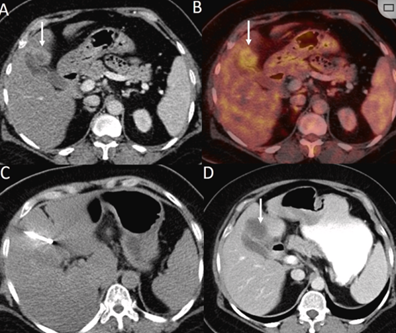

(a) 射頻消融后在病變邊緣顯示殘余增強(qiáng)。(b) 冷凍消融術(shù)中影像顯示冰球完全覆蓋病變。(c) 19個(gè)月后隨訪,沒有發(fā)生局部腫瘤進(jìn)展。完全消融率為97%(66/68);2名患者均接受了額外的冷凍消融,隨后實(shí)現(xiàn)完全消融。平均隨訪期為 12.8 個(gè)月(范圍:3-27 個(gè)月)。所有患者均接受影像復(fù)查(CT 或 MRI)。11個(gè)病灶(16.2%)檢測(cè)到局部腫瘤進(jìn)展,6、12和18個(gè)月時(shí)的累積局部腫瘤進(jìn)展率分別為4%、8.2%和20.5%。8例出現(xiàn)遠(yuǎn)處肝內(nèi)或肝外病變的患者接受經(jīng)動(dòng)脈化療栓塞、經(jīng)動(dòng)脈化療栓塞加射頻消融治療或全身化療。

回顧性納入2015 年至 2020 年期間49 名患者,23 名男性和 26 名女性。平均年齡為 67.5 歲(范圍 44-85 歲)。平均隨訪時(shí)間為 19.8 個(gè)月(范圍 1-60 個(gè)月)。對(duì) 54 個(gè)腫瘤病灶進(jìn)行了 64 次 冷凍消融 手術(shù)(50 個(gè)轉(zhuǎn)移癌和 14 個(gè) HCC)。平均腫瘤直徑為 2.15 cm(范圍 0.5-5 cm)。肝臟轉(zhuǎn)移灶來自結(jié)直腸 (n = 23)、乳腺 (n = 12)、胰腺 (n = 7)、肺 (n = 3)、甲狀腺 (n = 2)、胃 (n = 1)、卵巢 (n = 1) 和宮頸癌 (n = 2)。

79 歲男性,肝轉(zhuǎn)移(結(jié)直腸癌)腫瘤的完全消融病例

( a ) 軸向 MRI 和 ( b ) 軸向 CT 顯示肝S8段有一個(gè)16mm的病灶,鄰近肝緣。( c )冷凍消融期間CT顯示放置了2個(gè)冷凍探針,低密度冰球包圍病灶。(d)術(shù)后1個(gè)月隨訪 CT顯示冰球?qū)?yīng)的壞死區(qū)域,未見復(fù)發(fā)。(e)術(shù)后6個(gè)月的CT,壞死區(qū)域縮小,未見復(fù)發(fā)。(f)與基線影像(g)相比,12個(gè)月后的FDG-PET/CT顯示未見FDG攝取。

62歲女性,肝轉(zhuǎn)移(卵巢癌)腫瘤的完全消融病例(a)軸向CT顯示病變位置毗鄰心臟和上腔靜脈(黑色箭頭)。(b)術(shù)中軸向CT掃描:使用三個(gè)冷凍探針。1個(gè)月后的軸向(e)和冠狀位(f)增強(qiáng)CT掃描顯示低密度區(qū)域,由于肉芽組織反應(yīng)引起的邊緣增強(qiáng)。

技術(shù)成功100%,92% 的病灶中觀察到腫瘤完全消融。16 名患者 (33%) 出現(xiàn)局部復(fù)發(fā)。10 名患者 (20%) 因局部復(fù)發(fā)或腫瘤消融不完全而接受二次冷凍消融術(shù)。